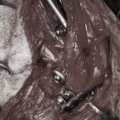

関節鏡

肩関節周囲の腫瘍病変の鑑別のため、関節鏡検査を実施した。上腕二頭筋腱を中心とした炎症像および滑膜炎が認められた。関節鏡下にて、上腕二頭筋腱の切断および炎症滑膜の焼烙処置を実施した。

<関節鏡写真:右肩関節内滑膜炎像>※写真は山口先生のご厚意による